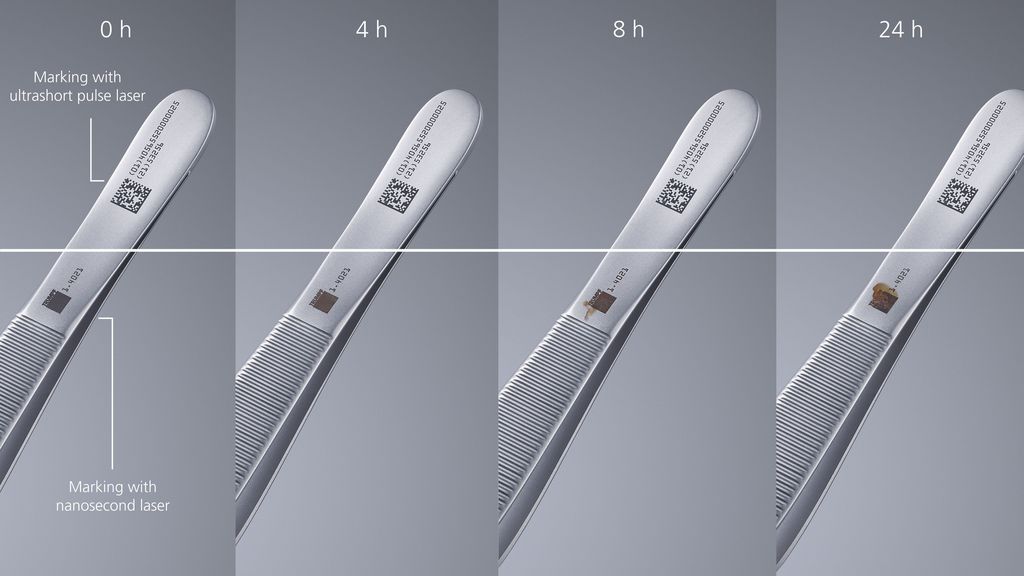

Black marking is a procedure in laser processing which causes extremely dark, high-contrast markings on a surface without material ablation. Extremely short laser pulses cause structures on the surface at the nanometer level. The microstructured surface ensures that light scattering is reduced, and creates a marking with constant depth and a consistent black color. When the laser pulses used for this marking are ultrashort, the color changes also remain corrosion-resistant within certain parameter ranges. The reason for this is that the use of ultrashort pulse lasers means that the heat-affected zone is extremely small, meaning that enough free chrome remains on the surface that a self-healing oxide film can form.

- Surface structure: Ultrashort pulse lasers with a pulse duration in the range of pico or femtoseconds provide the basis for corrosion-resistant black marking. It becomes possible to process materials with virtually no thermal or mechanical impact. This is because the laser pulse, and therefore the duration of the energy input, is so short that temperature transport to neighboring atoms does not even occur. This prevents thermal stress cracks which can occur in conventional annealing when the parameters are not considered. This is why it is referred to as "cold processing". The laser structures the material at the nanometer level.

- Oxide film: In addition to surface structuring, a chromium oxide film plays the second central role in corrosion-resistant black marking. The low exposure to heat in comparison to annealing with short-pulse lasers allows for a sufficient amount of chrome to remain on the surface, which promotes the self-healing process of the passive film. This creates more corrosion-resistant films with chromite (Fe2+Cr2O4) and magnetite (Fe3O4), as well as films consisting of a mixed phase: FeFe2-xCrxO4 (iron-chrome-spinel).